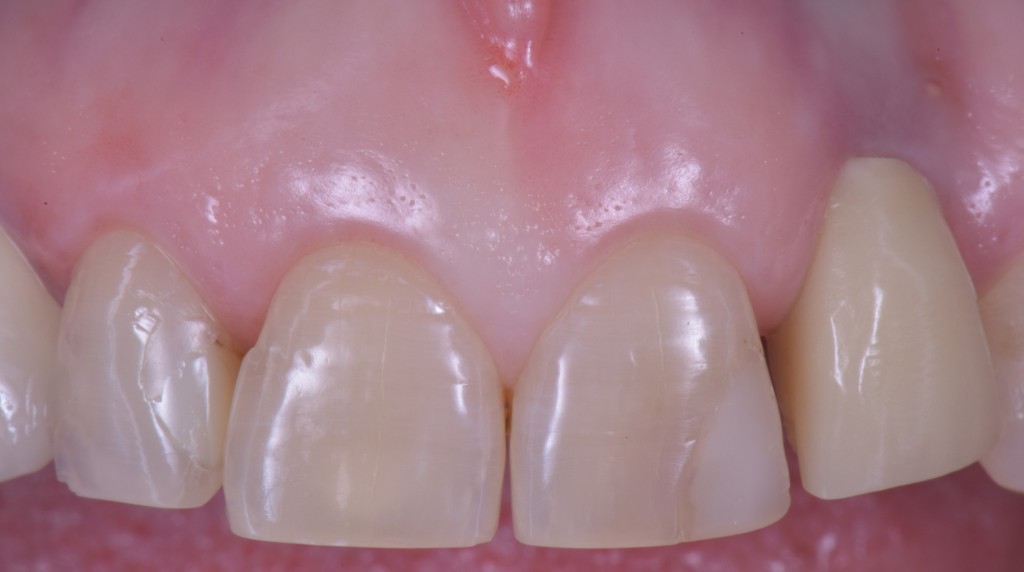

Un dente su impianto oggi ha la possibilità di avere questo aspetto

O questo, se vuoi un esempio frontale.

gestione dei tessuti molli - esempio frontali

Soprattutto se si parte da una condizione tissutale ottimale.